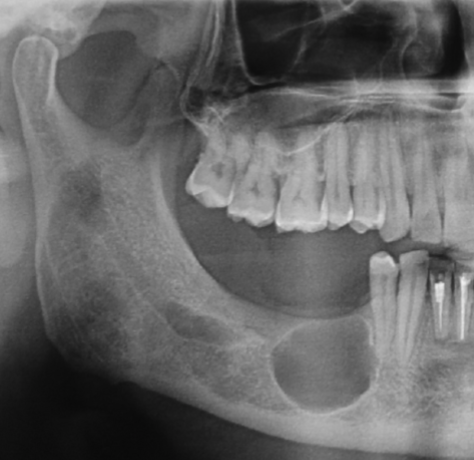

Assess the apical lucency at mesial root of 31

Normal Anatomy

Assess #32

Dentigerous Cyst